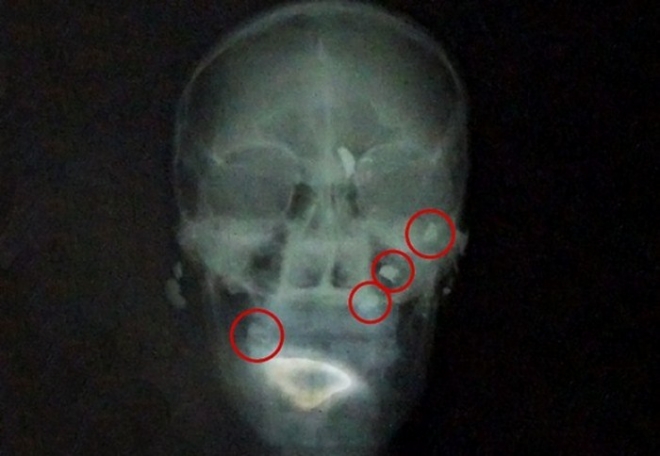

Um homem de 27 anos foi atingido por cinco tiros na cabeça na manhã de segunda-feira (5) em Chapadão do Sul (MS), a 325 km de Campo Grande. A vítima fez uma cirurgia no Hospital Municipal da cidade para retirada de uma das balas que estava alojada na nuca. Outras três balas continuam alojadas. O quinto tiro não ficou alojado.De acordo com a Polícia Militar (PM), o homem foi encontrado caído em uma rodovia perto da cidade por uma pessoa que passava pelo local. Ele foi levado para o posto policial e, segundo a corporação, chegou consciente, apesar dos ferimentos na cabeça.

O que mais chamou atenção foi que ele chegou andando ao hospital e não sabia que tinha levado cinco tiros na cabeça, conta o cirurgião. Dos cinco tiros, um ficou alojado na nuca, dois na mandíbula e um próximo ao ouvido. A quinta bala fraturou um osso nasal do homem, mas o projétil não ficou alojado, de acordo com o médico.

De acordo com o médico, as balas afetaram a parte subcutânea da pele e não atingiram nenhum osso nem o cérebro.